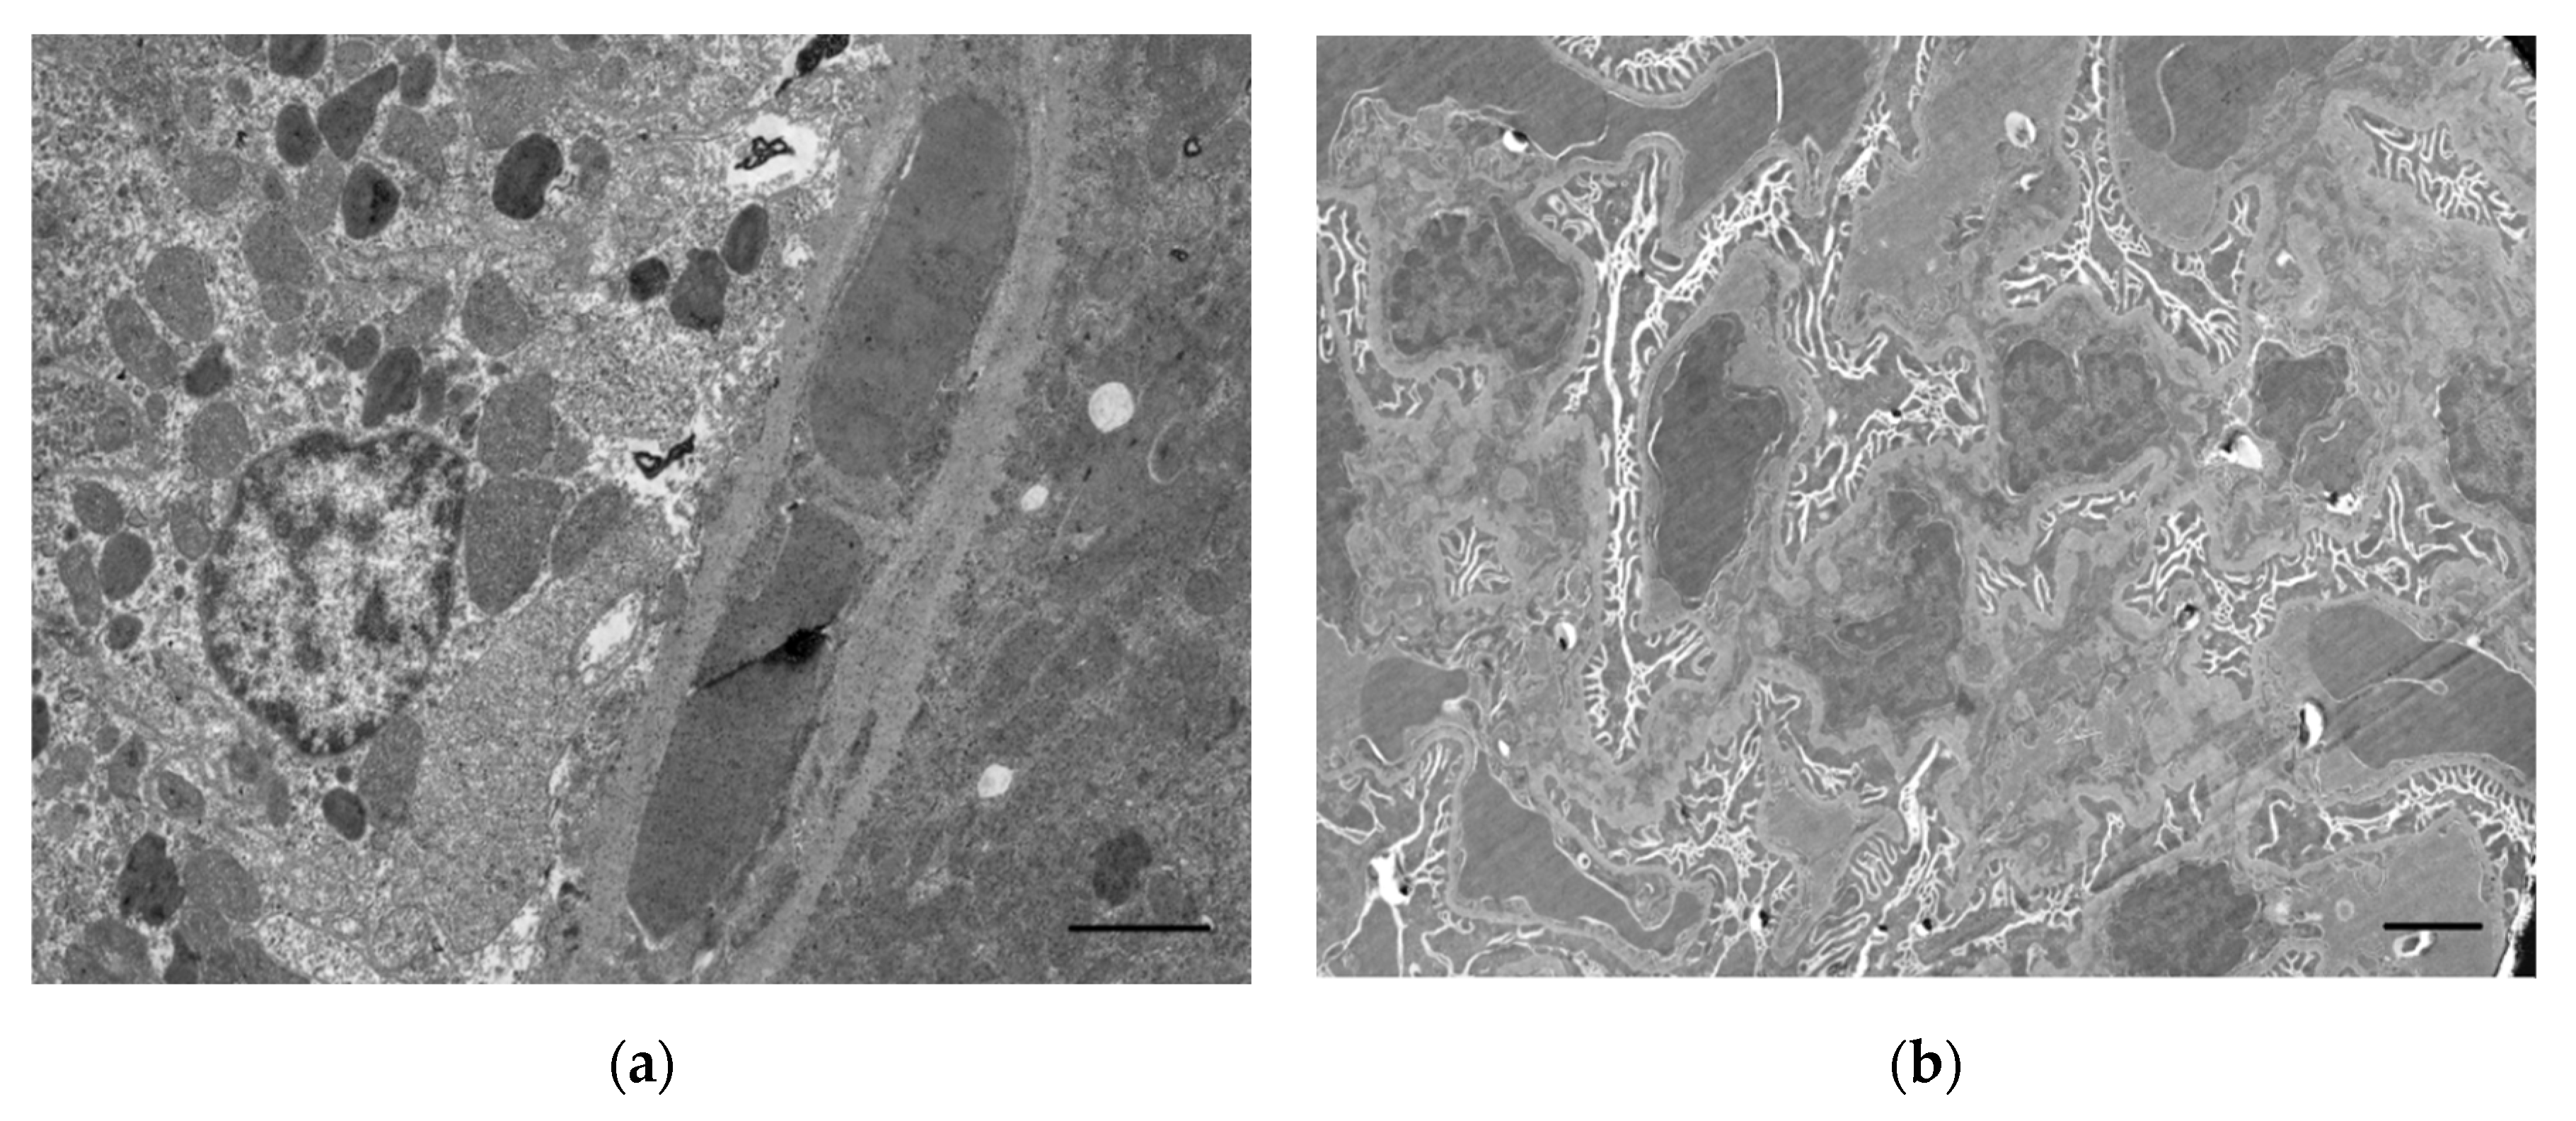

3. Histological and Ultrastructural Changes in the Kidneys

- Satar, S.; Satar, D.; Mete, U.O.; Suchard, J.R.; Topal, M.; Kaya, M. Ultrastructural effects of acute organophosphate poisoning on rat kidney. Ren. Fail. 2005, 27, 623–627. [Google Scholar] [CrossRef]

- Sobolev, V.E.; Korf, E.A.; Goncharov, N.V. The Rat (Rattus norvegicus) as a Model Object for Acute Organophosphate Poisoning. 5. Morphofunctional Alterations in Kidneys. J. Evol. Biochem. Physiol. 2019, 55, 302–312. [Google Scholar] [CrossRef]

- Sobolev, V.E.; Sokolova, M.O.; Jenkins, R.O.; Goncharov, N.V. Nephrotoxic Effects of Paraoxon in Three Rat Models of Acute Intoxication. Int. J. Mol. Sci. 2021, 22, 13625. [Google Scholar] [CrossRef]